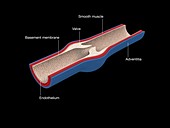

13435209 - Artery and vein, illustration

13443492 - Vein structure, illustration

13435208 - Artery and vein, illustration

13435190 - Artery, illustration

13443491 - Vein structure, illustration

13435191 - Artery, illustration

13443493 - Vein structure, illustration